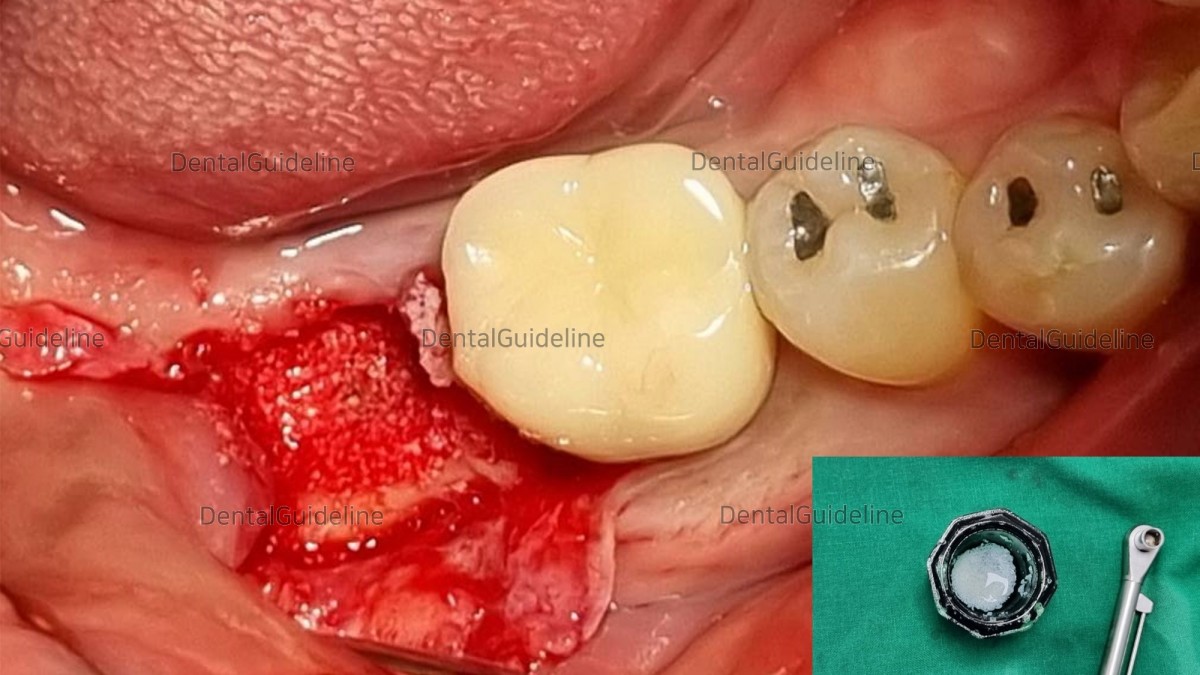

Implant placement day after 3 months of extraction.

Granulation tissue removal and osteotomy.

Initial stability was good enough.

Arum NB1 Ø5*L8.5

It is not a cover screw that fits the implant top, but a cover screw with a height of about 1~2mm.

GBR with Xenograft (porcine).

absorbable dural repair patch made of novel, composite material consists of synthetic material and gelatin.

suture.